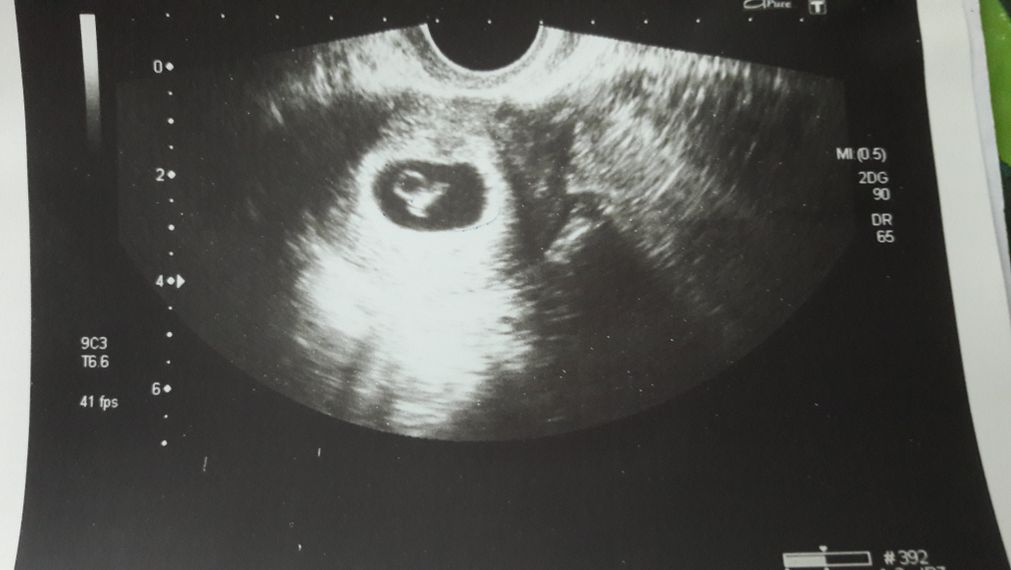

Развитие эмбриона на 8 неделе беременности